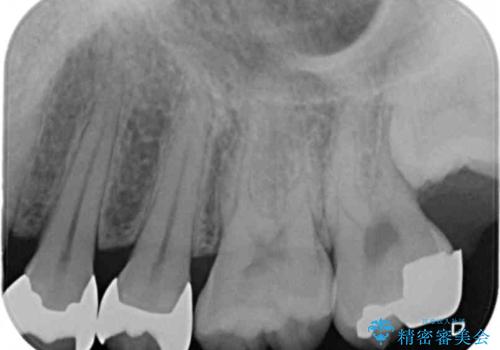

銀歯を目立たなくしたい セラミックインレーでの治療

- 外から見える範囲の銀歯のやり替えをご希望で来院されました。

セラミックインレーでの治療となります。

- 左上45 セラミックインレー 77,000円×2本 費用は治療当時の料金となります